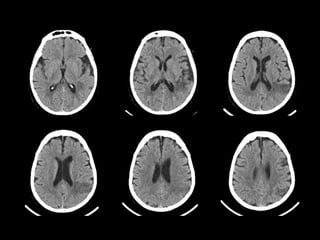

Bonus case -Answer  Mr. LR had a tiny right-sided subdural hematoma  Blood is seen along the left subdural space as well as in the falx cerebri anteriorly (arrows)  The hematoma is acute  Because of its small size, no immediate treatment was required  Follow-up CT scans showed resolution of the subdural hematoma Normal scan for comparison